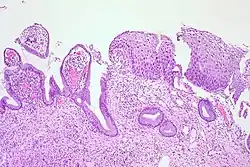

La NCI est classée en grades[14] :

| Grade histologique | Cytologie correspondante | Description | Image |

|---|---|---|---|

| 1 (catégorie I) | Lésion malpighienne intra-épithéliale de bas grade (LSIL) |

|

| 2/3 | Lésion malpighienne intra-épithéliale de haut grade (HSIL). |

| |

| 2 (grade II) |

| ![]() | |

| 3 (grade III) |

| ![]() |